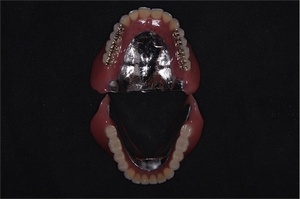

コンビネーション (11)

クーゲルホックAT義歯 |  ジルコニアブレード義歯 |